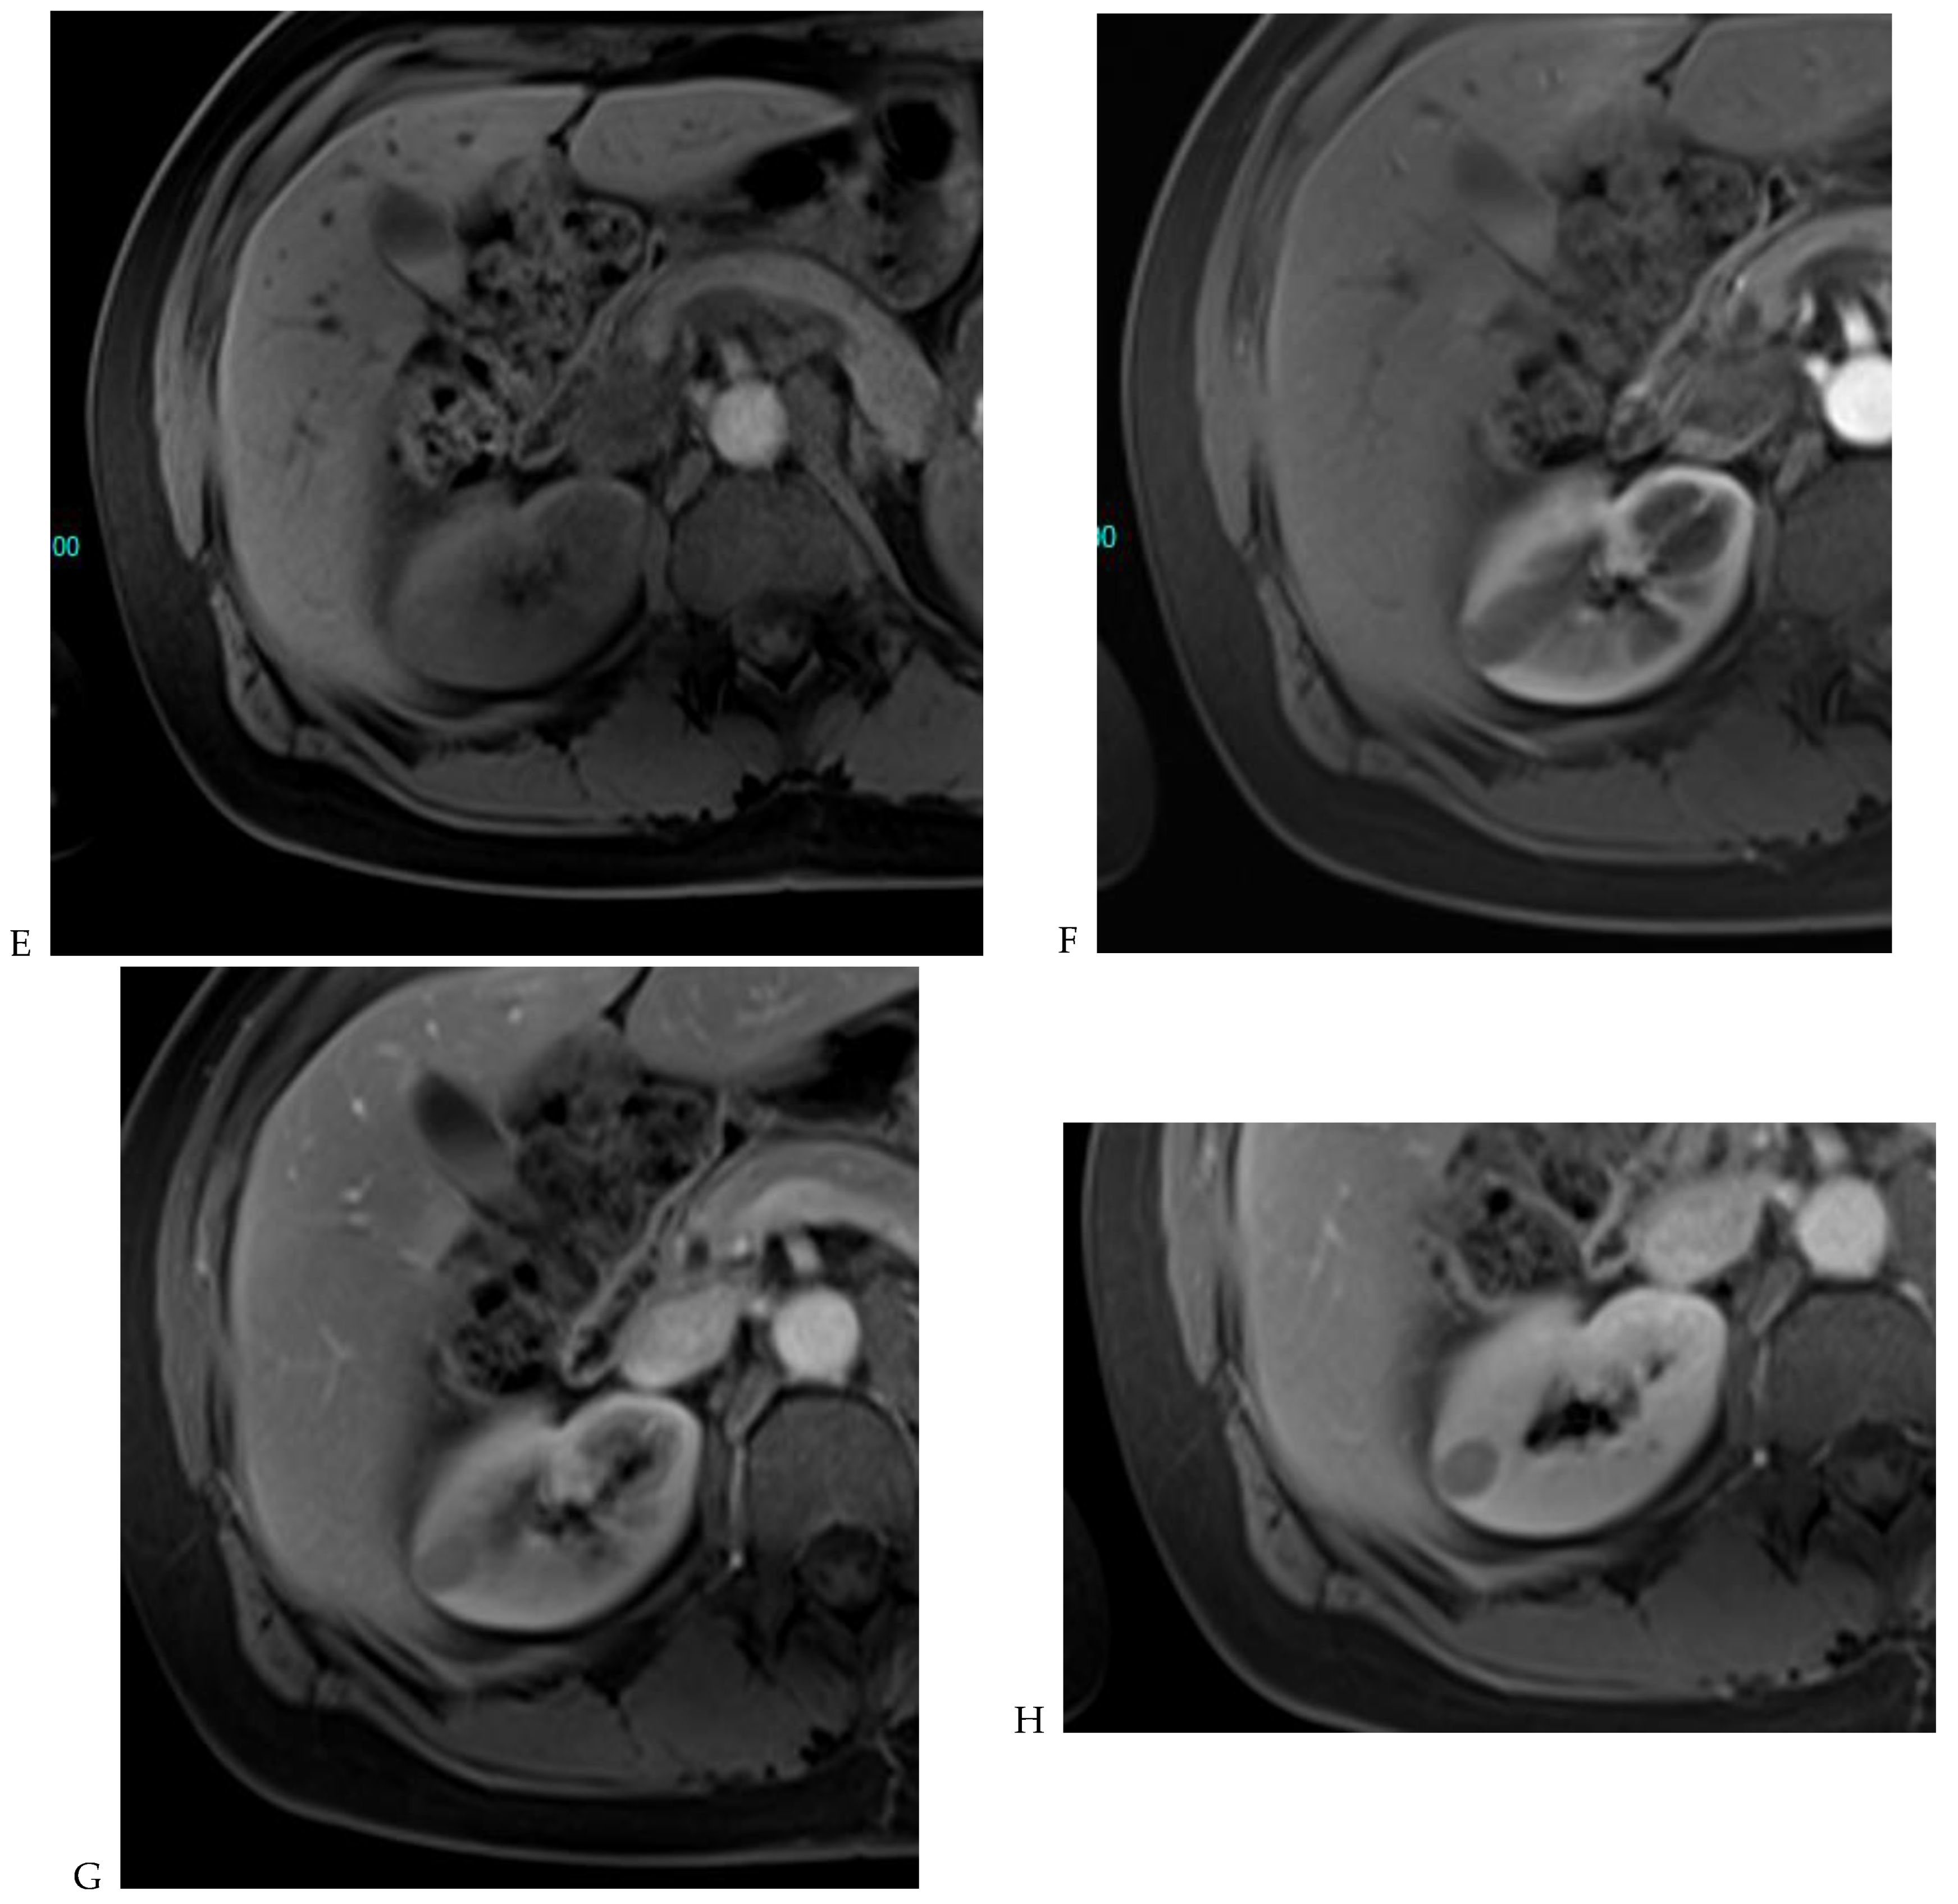

Figure 8.

Same lesion as Figure 3. Chromophobe renal cell carcinoma in the left kidney of a 68-year-old-woman. (A) Axial T2-weighted fast SE image shows the exophytic heterogeneous isointense renal mass with a posterior hyperintense area. Transverse in-phase (B,C) opposed-phase MR images show no significant loss of signal intensity on the opposed-phase image. (D) The ADC map shows restriction of tumor diffusion into the renal mass. Transverse nonenhanced (E) and gadolinium-enhanced T1-weighted gradient-echo spoiled MR images in (F) corticomedullary, (G) nephrographic, (H) and delayed phase images show a mid-intense enhancement of the lesion without visible washout.